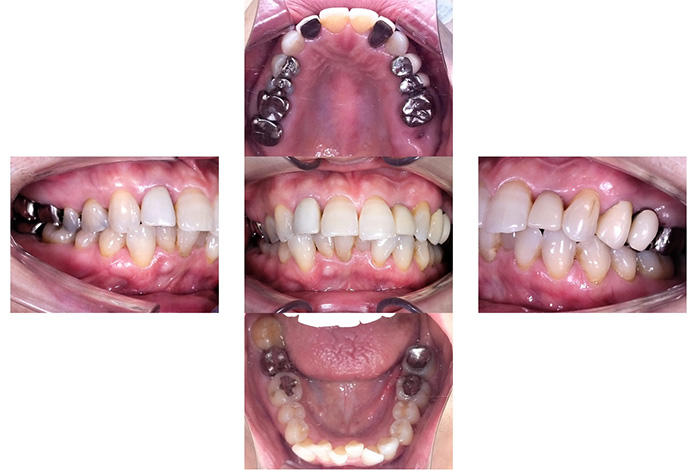

Before

After

【矯正治療】マウスピース型矯正装置(インビザライン)による全顎矯正

【補綴治療】詳細は表内の費用欄に掲載

【矯正治療】10か月

【補綴治療】約5か月

【矯正治療】12回

【補綴治療】14回

【矯正治療】¥957,000(税込)

【補綴治療】

右上臼歯部2本・左下臼歯部2本にインプラント治療を行った症例です。

欠損部に対しインプラントを埋入し、咀嚼機能の回復と咬合バランスの改善を行いました。周囲歯への負担を抑えながら、固定性のある補綴装置により安定した噛み心地を目指した治療です。

【右上臼歯部インプラント治療】インプラント埋入手術および上部構造装着(2本)

【左下臼歯部インプラント治療】インプラント埋入手術および上部構造装着(2本)

【右上臼歯部インプラント治療】約4か月

【左下臼歯部インプラント治療】約3か月

【右上臼歯部インプラント治療】8回

【左下臼歯部インプラント治療】8回

【右上臼歯部インプラント治療】1本 ¥555,500(税込)

※本症例は2本

【左下臼歯部インプラント治療】1本 ¥555,500(税込)